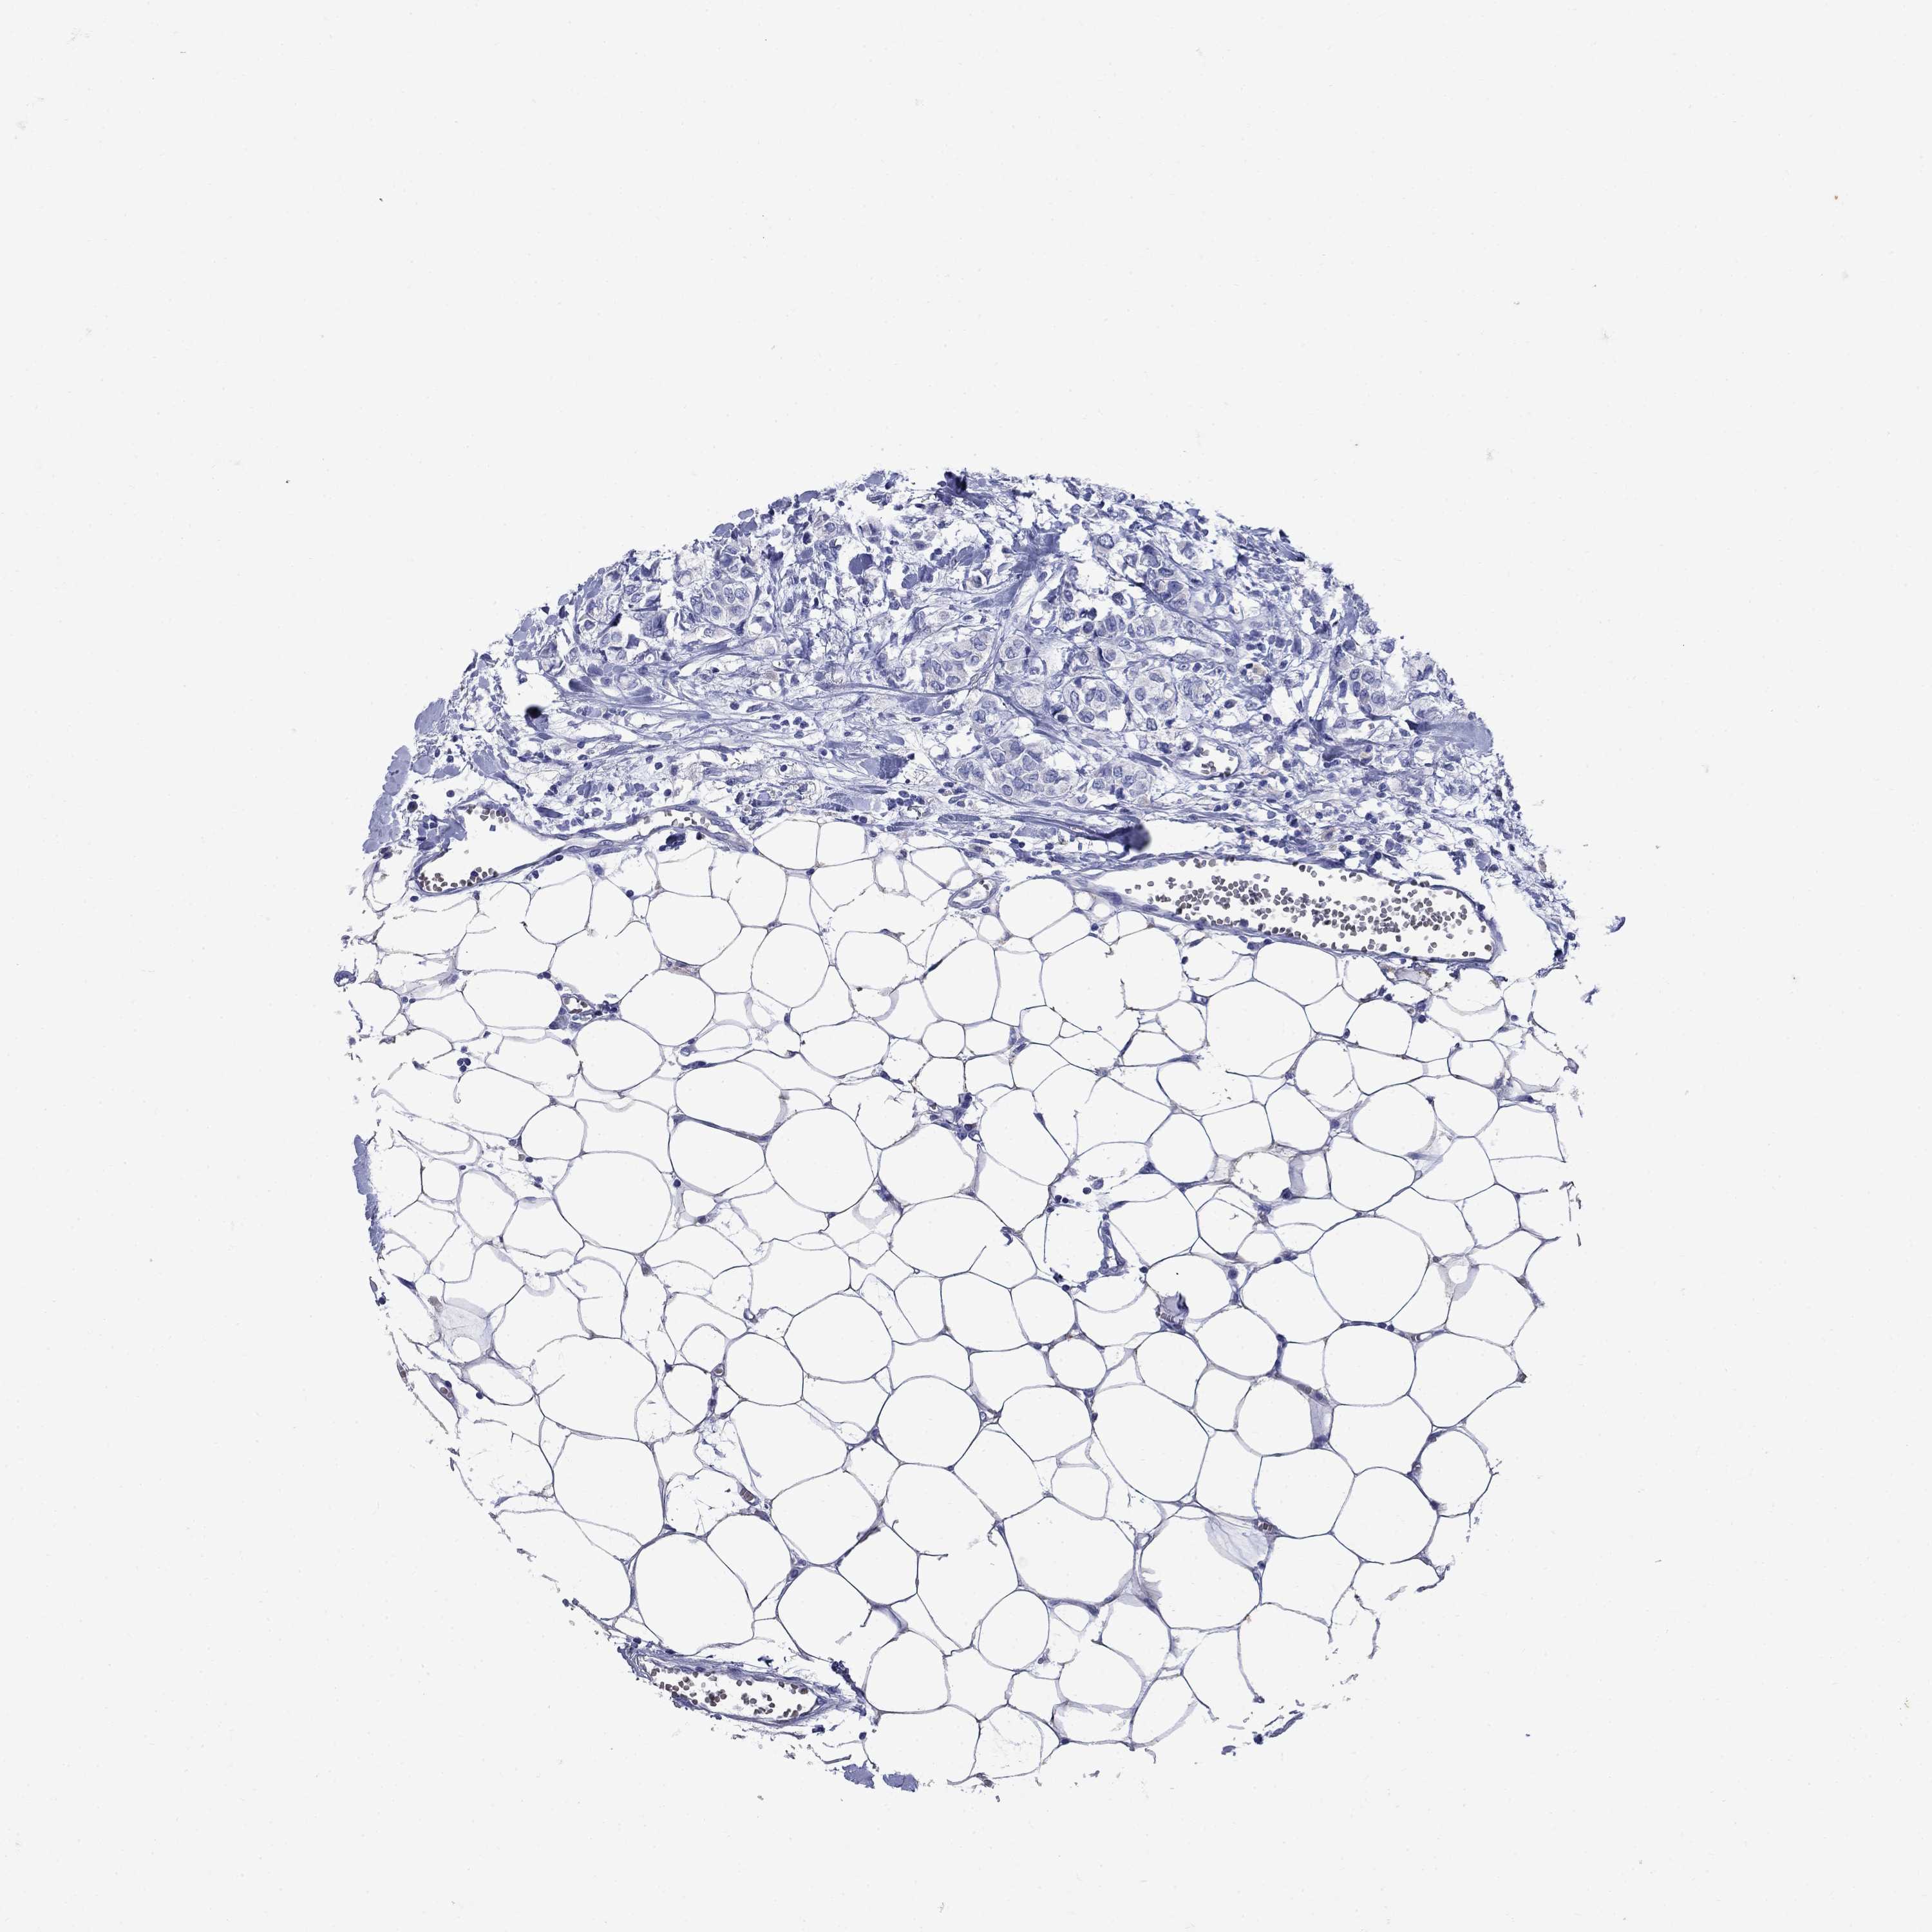

Breast cancer

Human cancer